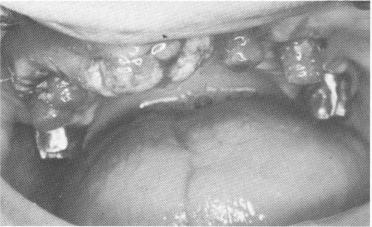

Fig. 11-131. Five days later (11 days postoperatively) the one-piece metal casting was fitted over the abutments.

4 One piece metal casting fitted over maxillary abutments